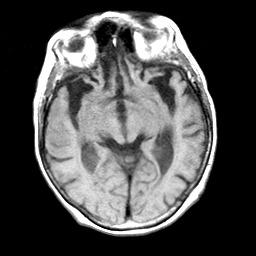

Pick's Disease, MR Study mr-t1 -- Slice #9

[Home][Help][Clinical] Slice 9